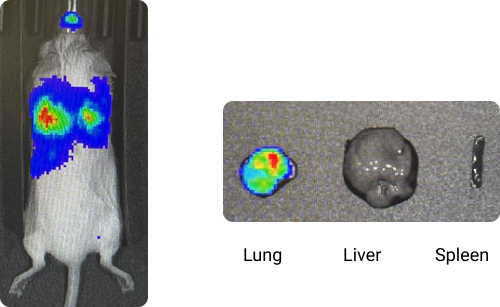

In vivo and ex vivo IVIS images 4 hours after inhalation of

nebulized Cytofinity™ LNPs loaded with Luc-mRNA